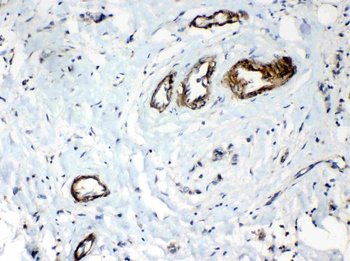

10 μg, 100 μg - Anti-S100 alpha 6/S100A6 Antibody [orb315184]

FC, ICC, IF, IHC, WB

Human, Mouse, Rat

Rabbit

Polyclonal

Unconjugated

10 μg, 100 μg - Anti-HSD11B2 Antibody [orb316541]